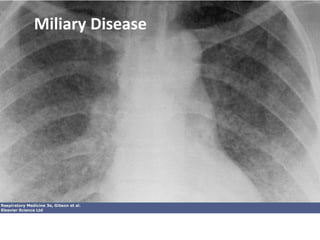

Milliary Tuberculosis

- Uncontrolled haematogenous dissemination

- Progressive primary or reactivation

- Requires impaired immunity thus 50% in infants, elderly

and HIV+

- Clinical course variable; fumlinant to subacute

- Non specific presentation; failure to thrive ,night sweats,

pyrexia, ARDS

- Difficult to diagnose, 20% post mortem

- Hepatomegaly , ascites, deranged liver function

- Meningeal disease in 15 – 20%

• Multiorgan failure, septic shock, and

respiratory distress, followed by death, may

occur